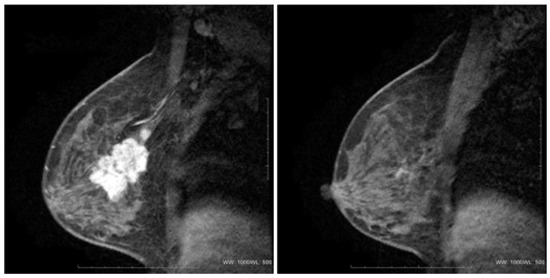

Advances in Medical Image Processing for Early Breast Cancer Detection: Classical Techniques and Deep Learning Perspectives

Breast cancer is the most common malignancy among women and a leading cause of cancer-related mortality, making early and accurate detection essential. This review summarises advances in breast imaging and computational diagnostics across mammography, ultrasound, and magnetic resonance imaging (MRI), highlighting challenges in [...] Read more.

Breast cancer is the most common malignancy among women and a leading cause of cancer-related mortality, making early and accurate detection essential. This review summarises advances in breast imaging and computational diagnostics across mammography, ultrasound, and magnetic resonance imaging (MRI), highlighting challenges in differentiating benign from malignant lesions and identifying rarer tumour types. Key preprocessing steps—denoising, deblurring, and contrast enhancement—are reviewed as they improve image quality prior to analysis. Classical methods (e.g., thresholding, edge detection, and region growing) are compared with deep learning approaches for segmentation and classification. CNNs, RNNs, and emerging transformer-based models consistently outperform handcrafted pipelines, with representative studies reporting 5–15% gains in AUC/accuracy and deep models achieving AUC > 0.85–0.95 on several benchmarks. The review also discusses dataset constraints, common evaluation metrics (AUC, Dice, sensitivity, specificity), and clinical translation barriers such as interpretability and domain shift. Overall, AI-driven methods show strong potential to enhance early detection and support improved breast cancer outcomes. Full article

Show Figures

Figure 1